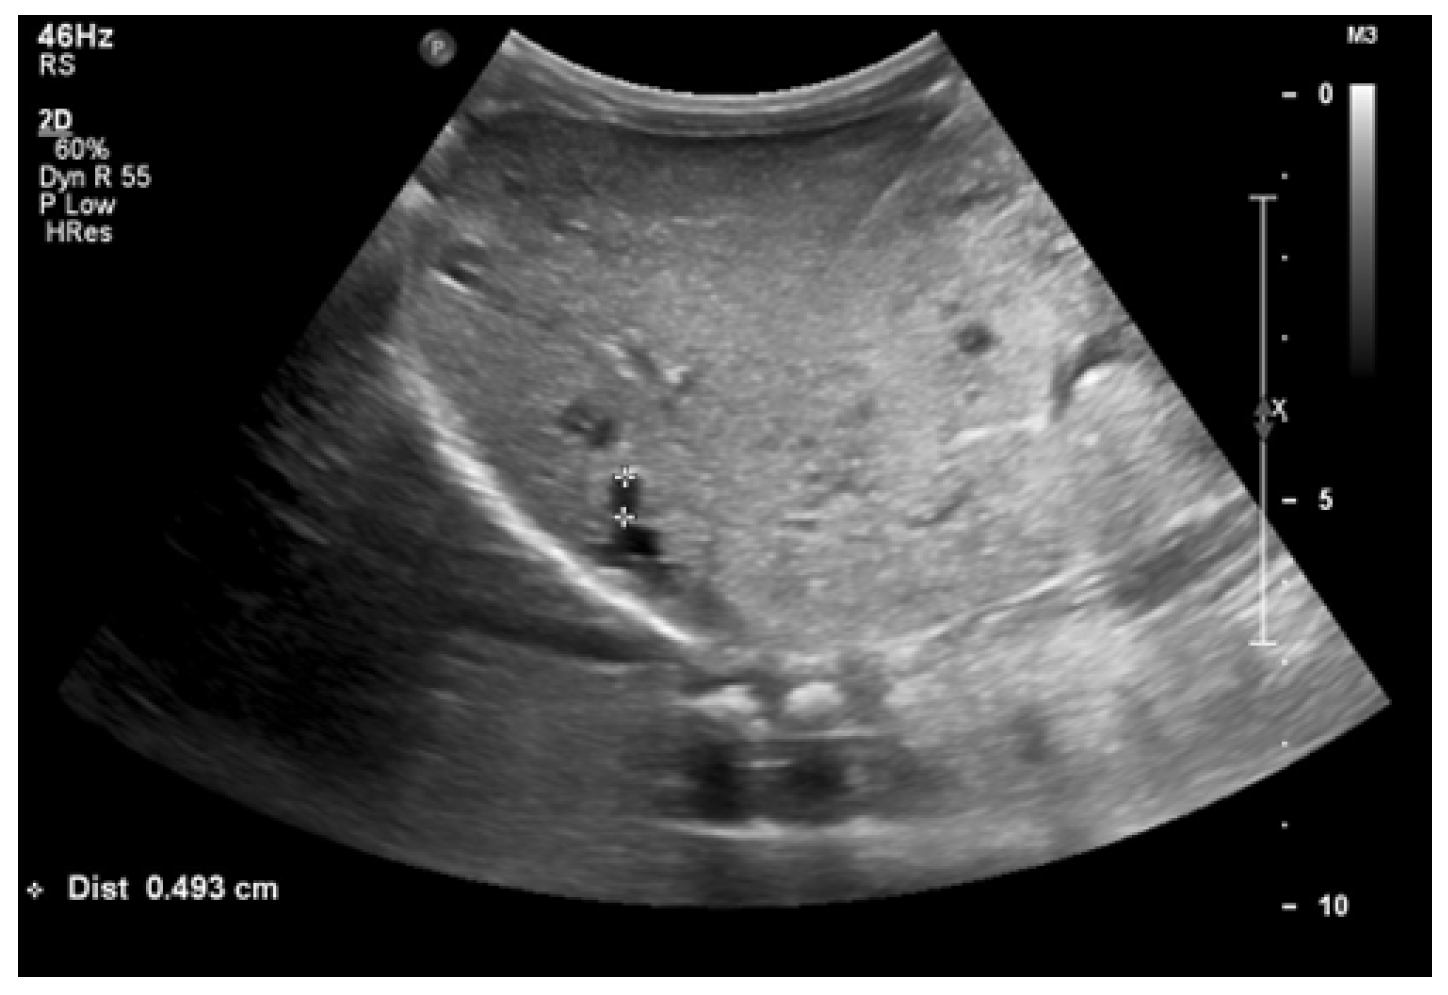

Currently, the boy is 5 years old. The US is similar to the previous one: elevated kidneys length (right: 130 mm (z-score 6.19); left: 133 mm (z-score 6.50)), with increased echogenicity, blurred corticomedullary differentiation, and multiple cysts with a maximum diameter up to 13–15 mm. The liver has a normal size, with numerous cysts up to 16 mm in diameter, with the largest cluster of cysts measuring 43 × 23 × 31 mm (Figure 3 and Figure 4). Laboratory tests show increased creatinine 0.79 mg/dL, urea 69,6 mg/dL, cystatin C 1.71 mg/L, uric acid 6.9 mg/dL, urine albumin to creatine ratio (ACR) 118.6 mg/g, and decreased GFR 55 mL/min/1.73 m2—stage III CKD. Other tests, including electrolytes, liver function, and urinalysis, were normal. The boy demands antihypertensive multi-drug therapy: angiotensin-converting enzyme inhibitors (ACEIs), calcium channel blockers, and beta-blockers.

Figure 4. Ultrasonography of the liver with the largest cluster of cysts.